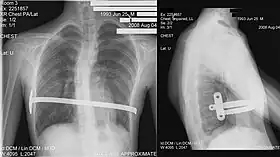

His two-stage procedure, widely known as the Nuss procedure, involves slipping in one or more concave steel bars into the chest, underneath the sternum.[56]

The bar is flipped to a convex position so as to push outward on the sternum, correcting the deformity. The bar usually stays in the body for about two years, although many surgeons are currently moving toward leaving them in for up to five years. When the bones have solidified into place, the bar is removed through outpatient surgery.

Although initially designed to be performed in younger children of less than 10 years of age, whose sternum and cartilage is more flexible, there are successful series of Nuss treatment in patients well into their teens and twenties.[57]